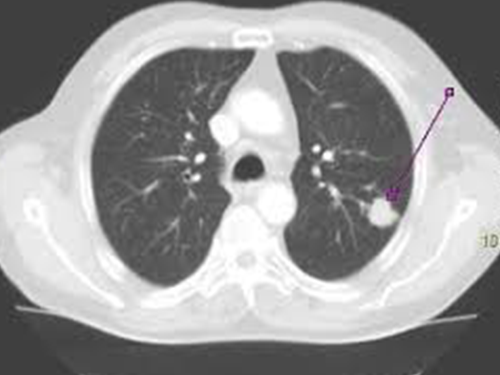

Akciğerde leke, röntgen veya bilgisayarlı tomografi (BT) gibi görüntüleme yöntemleriyle akciğer dokusunda görülen anormal görünümlerdir. Bu lekelerin nedenleri oldukça çeşitlidir ve her zaman ciddi bir sorunu işaret etmez. İşte akciğerde leke oluşumuna yol açabilen bazı yaygın nedenler:

• Akciğer Tümörleri:

• Akciğer kanseri: Akciğerde lekelere neden olabilen kötü huylu tümörlerdir.

• İyi huylu tümörler: Nadiren de olsa iyi huylu tümörler de lekelere yol açabilir.

• Diğer Nedenler:

• Akciğer fibrozisi: Akciğer dokusunda sertleşme ve yara izi oluşumu.

• Akciğer embolisi: Akciğer damarlarında tıkanıklık.

• Akciğer ödemi: Akciğerlerde sıvı birikimi.

• Geçirilmiş enfeksiyonların bıraktığı izler.